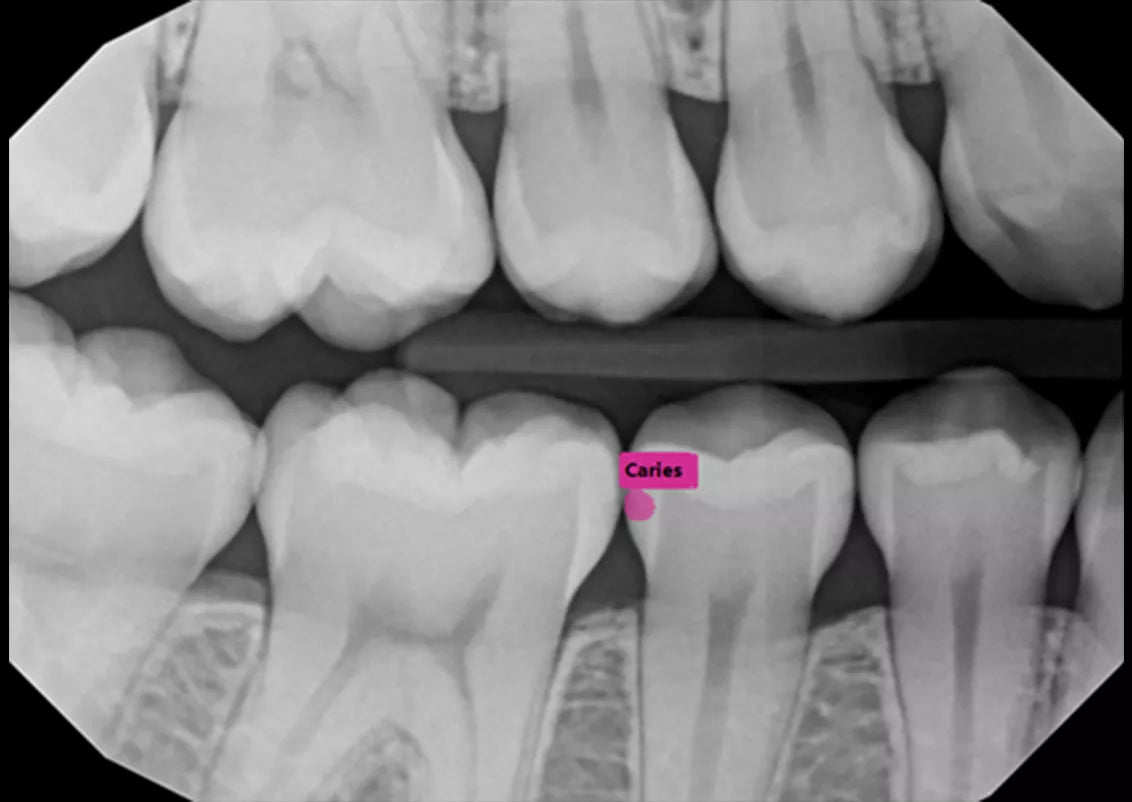

Built into DEXIS™ Imaging Suite Software, the DEXassist Solution provides assisted intelligence with a single click. This new solution enables users to identify up to six dental findings on 2D x-ray images.

The DEXassist Solution integrates AI features from DTX Studio™ Clinic into DEXIS Imaging Suite Software.